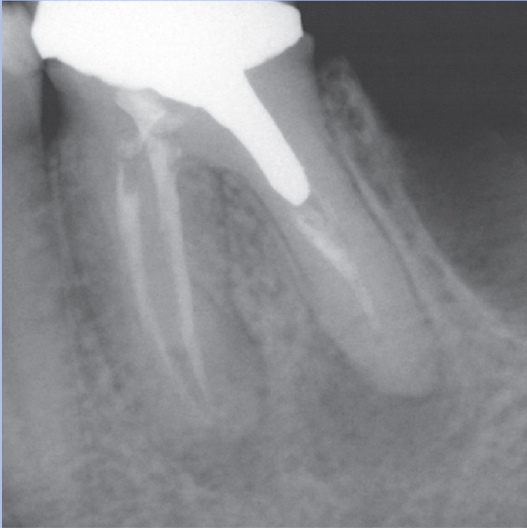

After

After Root Canal treatment